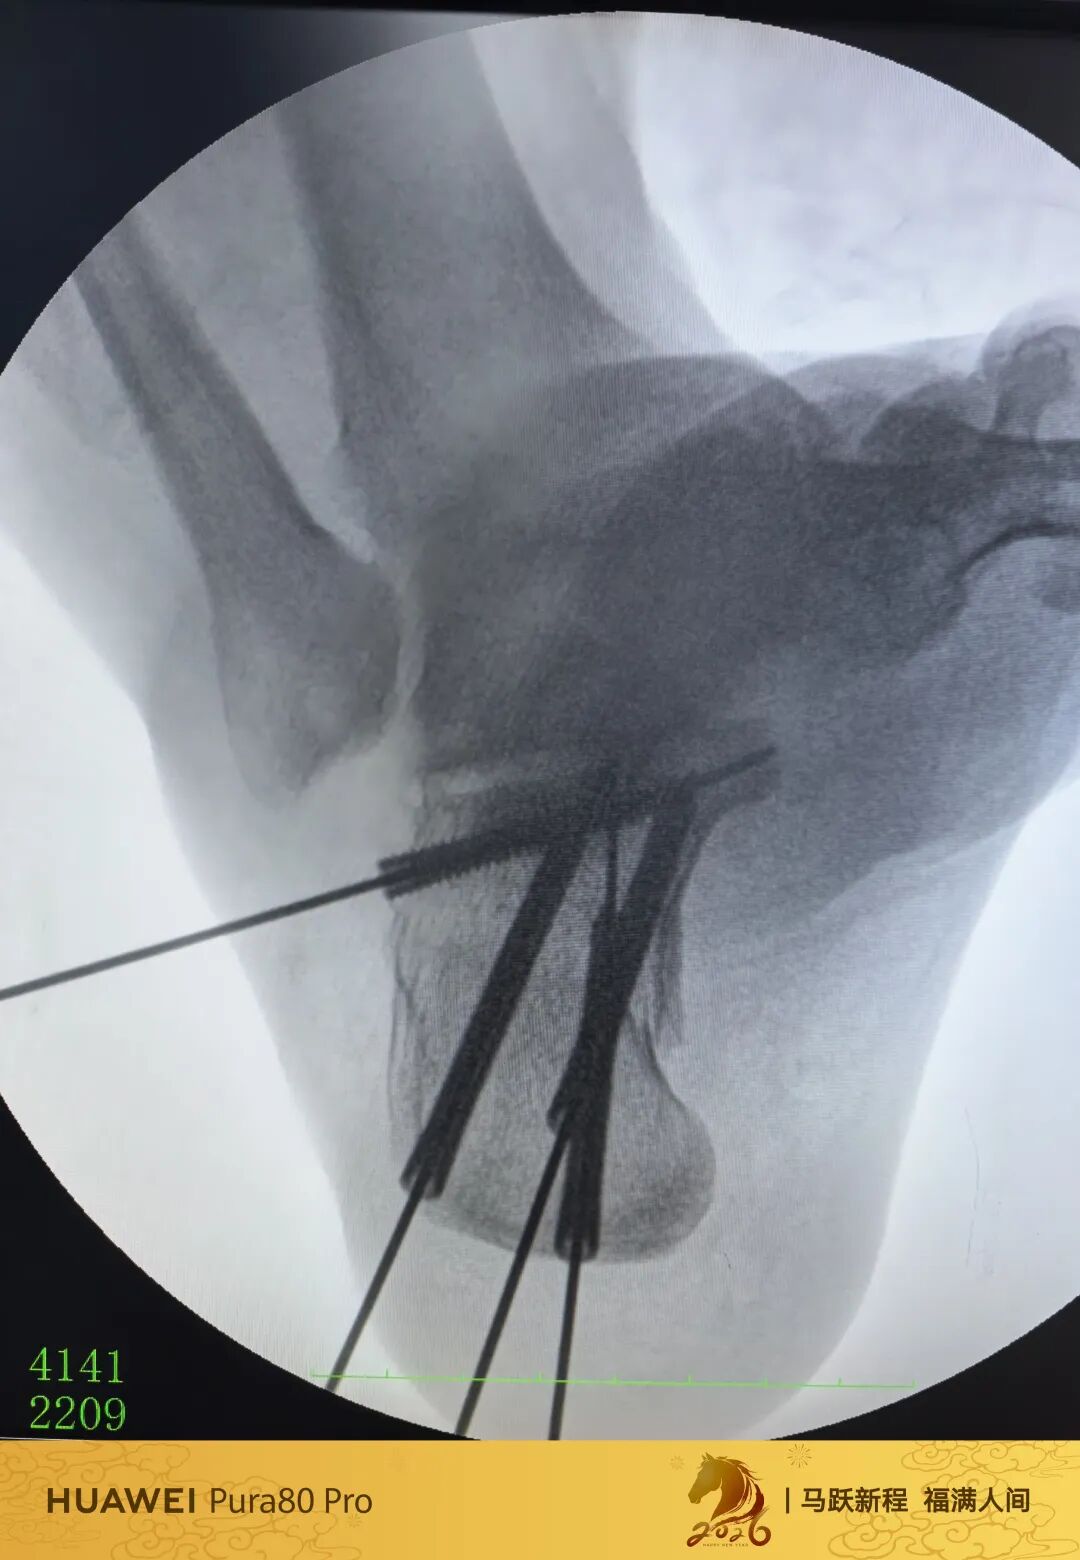

第60例跟骨微创了,虽然已经彻底放手,尽量只动嘴,但还是有小问题小瑕疵,无法完全避免。